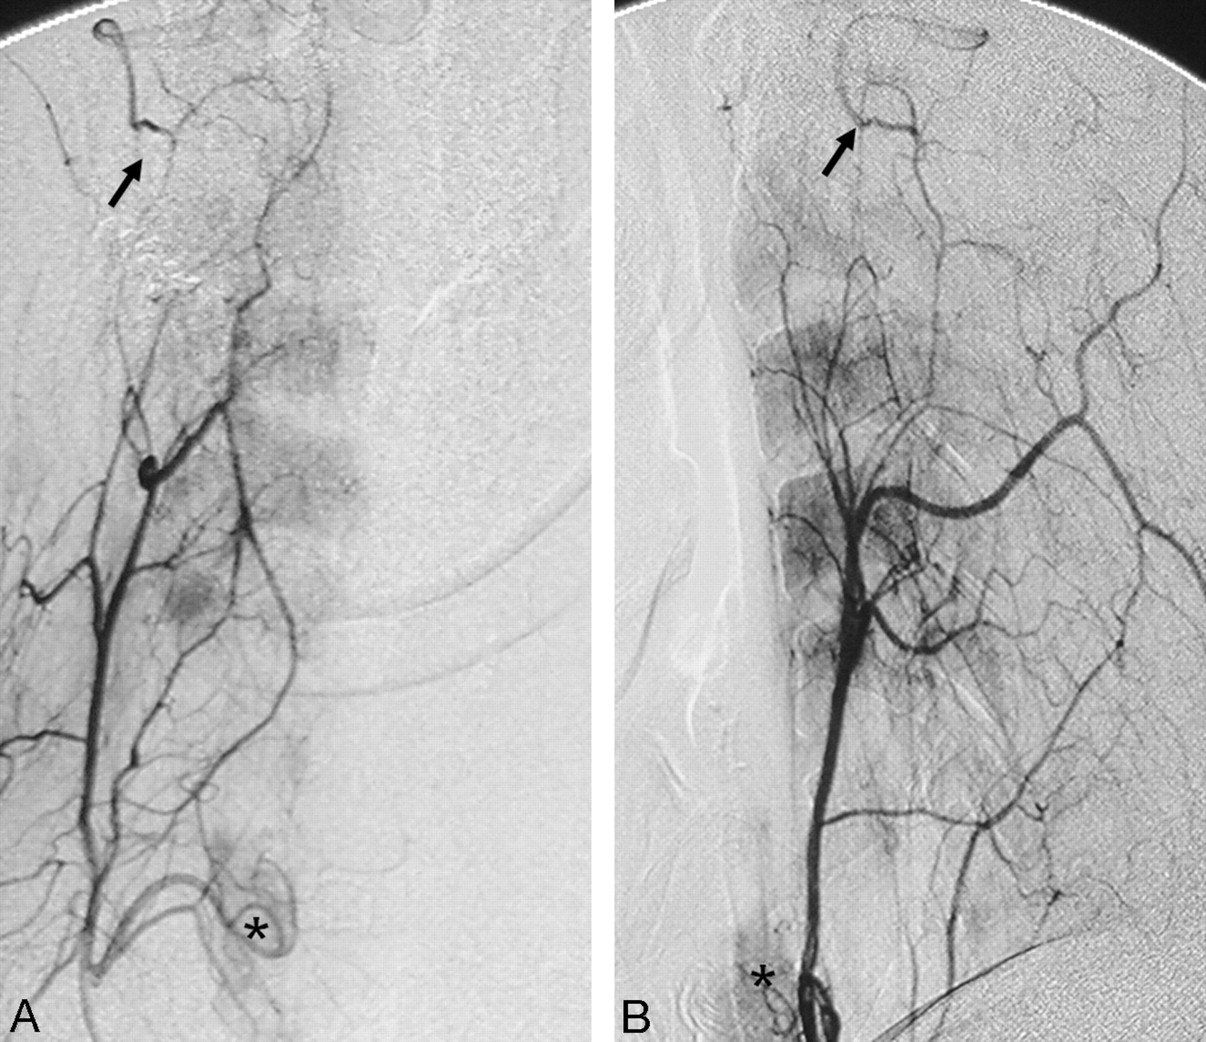

Right ascending cervical angiogram in anteroposterior (A) and lateral (B) views demonstrates anastomosis with the vertebral artery at the C2 level (black arrows). Note the inferior thyroidal artery with capillary staining of the thyroid gland (asterisks), which also arises from the thyrocervical trunk.